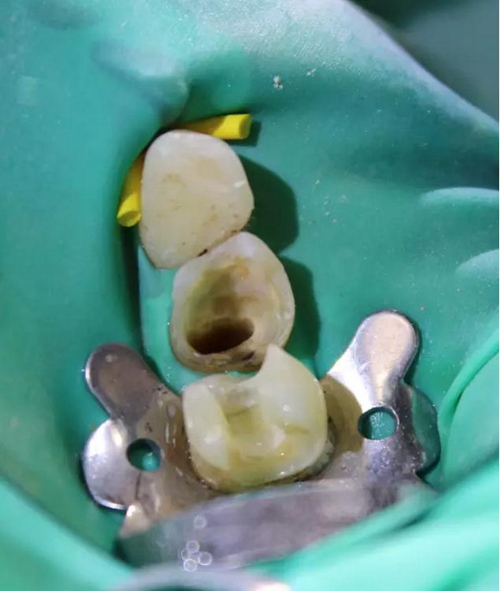

圖3 核修復完畢(橡皮障未去除)。這種2層堆疊技術非??焖?,且調(牙合)更少。

圖6 左下4和左下5使用瓷納美通用修復型樹脂及SDR修復后的效果。